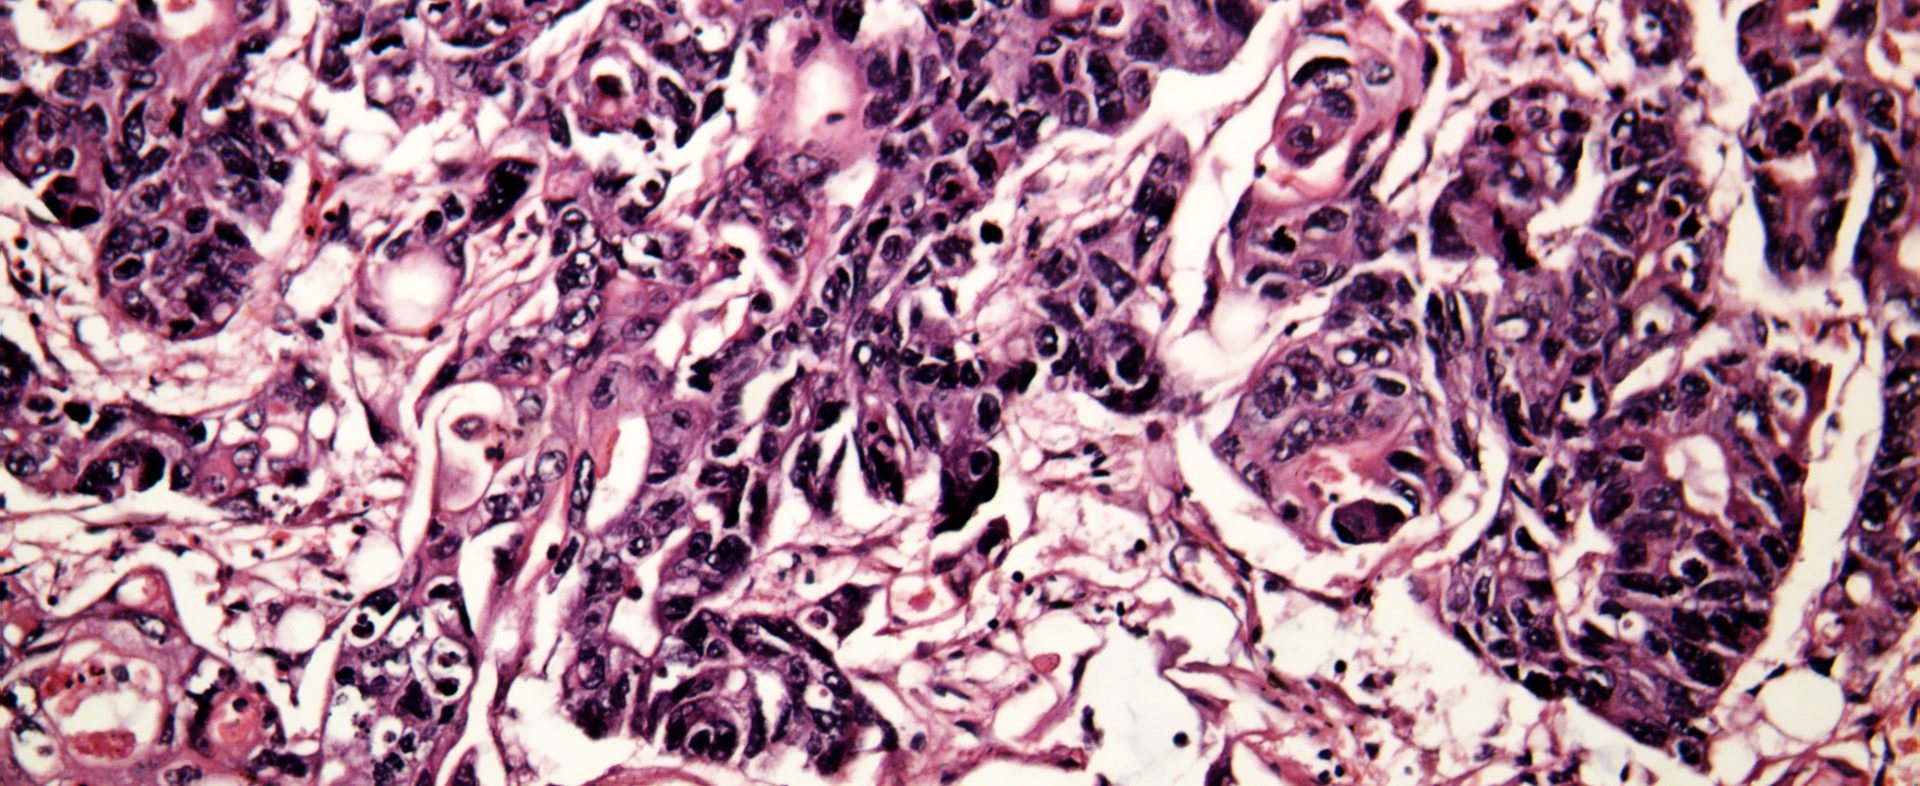

Zwei Millionen neue Krebserkrankungen jährlich – verursacht durch Viren und Bakterien

Einige Krankheitserreger stellen einen hohen Risikofaktor für bestimmte Krebsarten dar: Von den 14 Millionen neuen Krebsfällen im Jahr 2012 waren 2,2 Millionen auf zehn Krankheitserreger zurück­zuführen. Die meisten dieser infektionsbedingten Krebserkrankungen betrafen ärmere Länder.